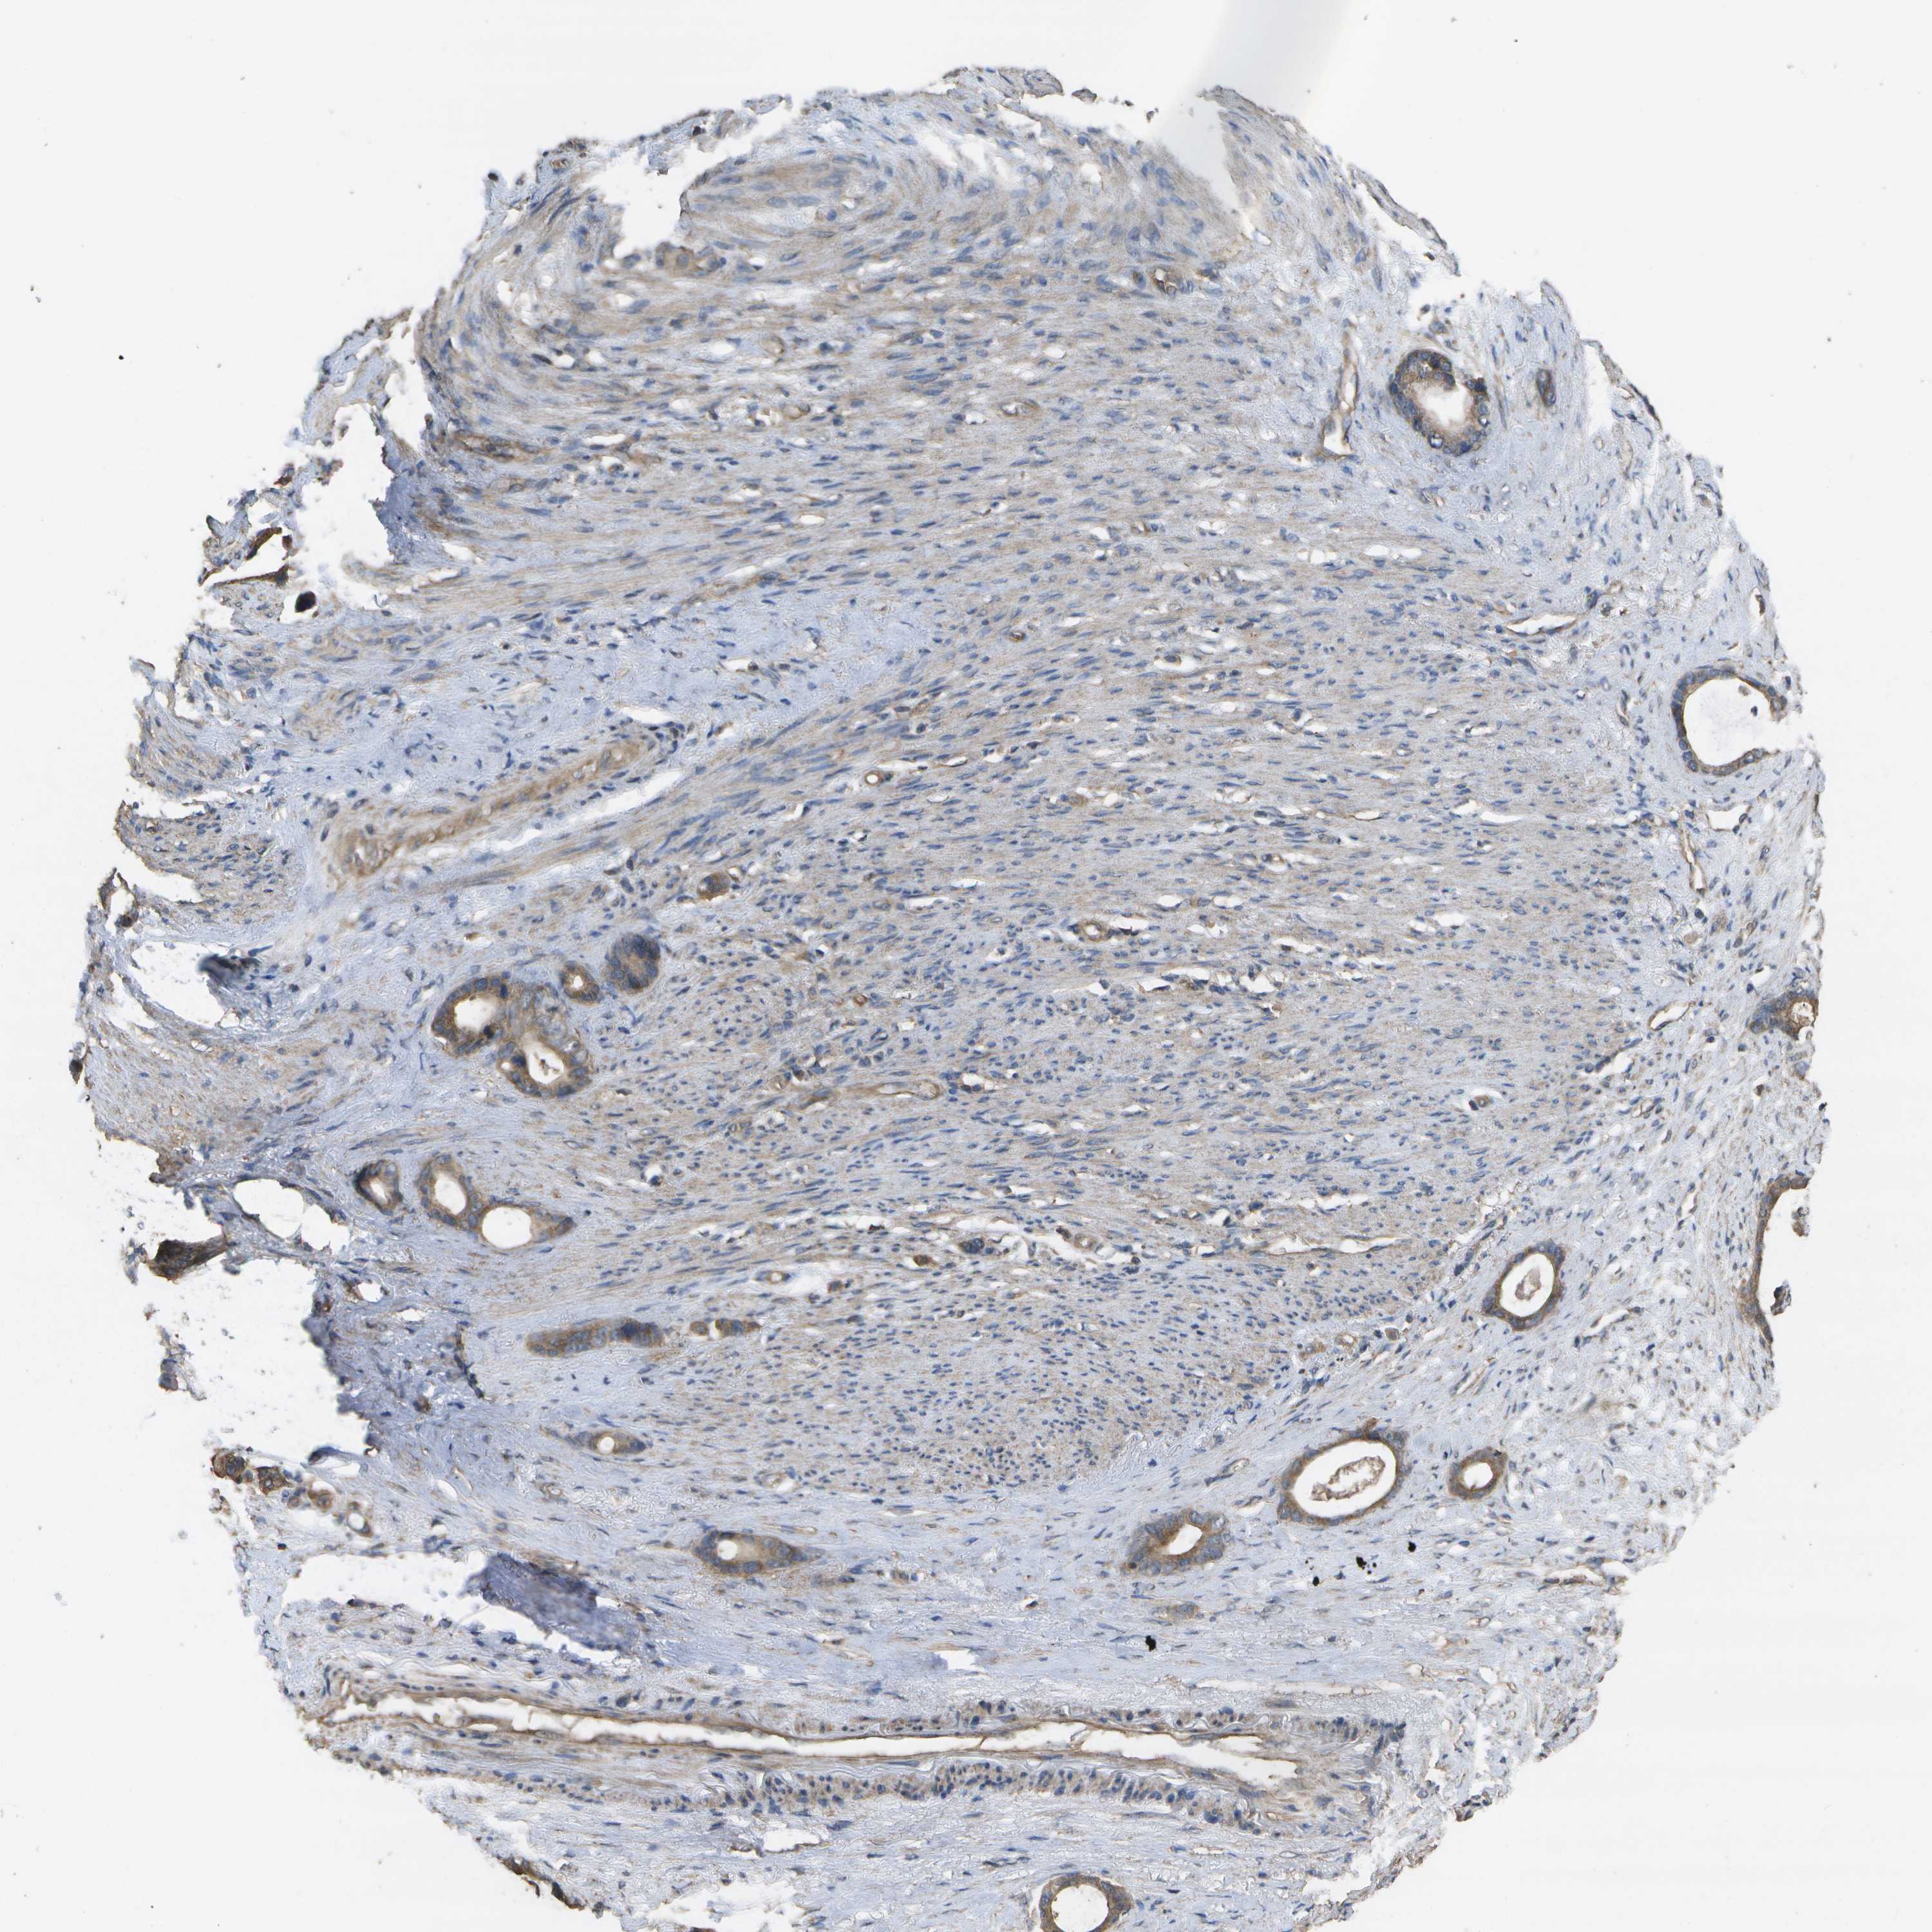

STOMACH CANCER - Protein expressioni

A mouse-over function shows sample information and annotation data. Click on an image to view it in a full screen mode. Samples can be filtered based on level of antibody staining by selecting one or several of the following categories: high, medium, low and not detected. The assay and annotation is described here.

Antibody stainingi

Antibody staining in the annotated cell types in the current human tissue is reported as not detected, low, medium, or high, based on conventional immunohistochemistry profiling in selected tissues. This score is based on the combination of the staining intensity and fraction of stained cells.

Each image is clickable and will lead to virtual microscopy that enables deeper exploration of all samples and also displays staining intensity scores, fraction scores and subcellular localization as well as patient and tissue information for each sample.

Antibody CAB017714

Staining

High

Medium

Low

Not detected

Intensity

Strong

Moderate

Weak

Negative

Quantity

>75%

75%-25%

<25%

None

Location

Nuclear

Cytoplasmic/membranous

Cytoplasmic/membranous,nuclear

Adenocarcinoma, NOS

Adenocarcinoma, High grade